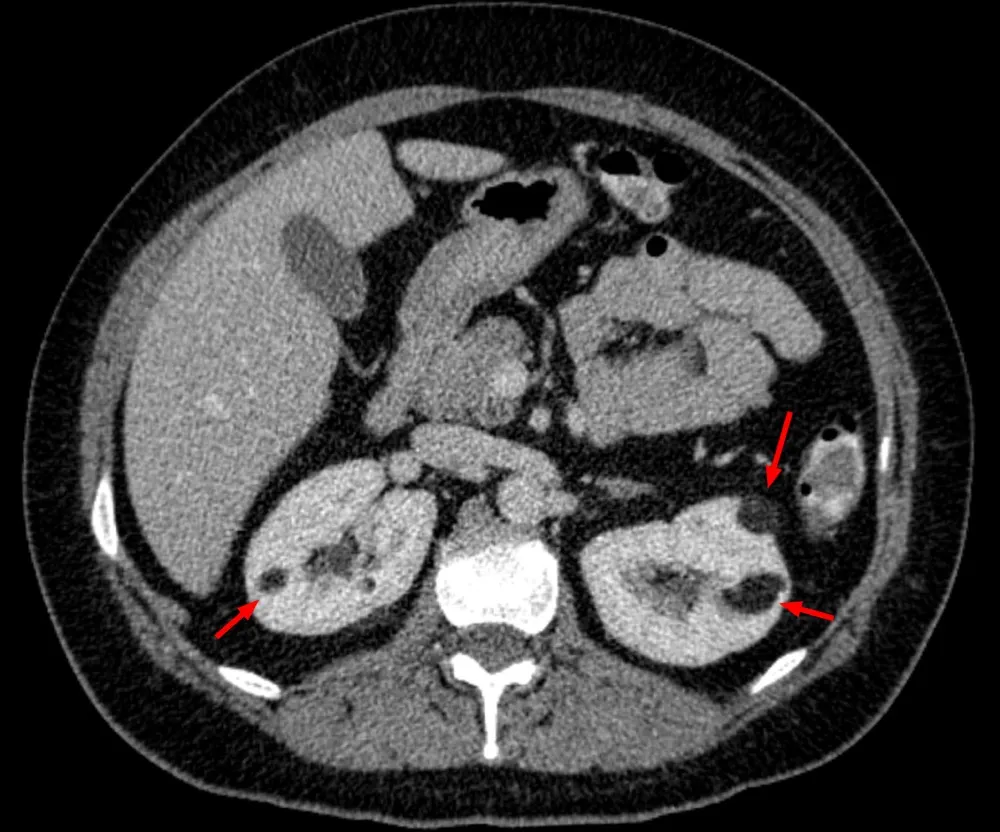

Angiomiolipoma renal, quando pensar em Esclerose Tuberosa?